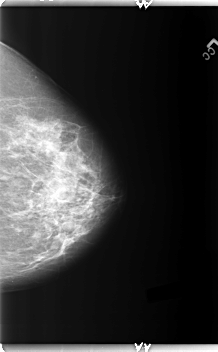

B_3148_1.LEFT_MLO

LEFT_CC LINES 5968 PIXELS_PER_LINE 3704 BITS_PER_PIXEL 12 RESOLUTION 50 NON_OVERLAY

LEFT_MLO LINES 5944 PIXELS_PER_LINE 3184 BITS_PER_PIXEL 12 RESOLUTION 50 NON_OVERLAY

FILE: B_3148_1.RIGHT_CC.OVERLAY

TOTAL_ABNORMALITIES 2

ABNORMALITY 1

LESION_TYPE CALCIFICATION TYPE AMORPHOUS-PLEOMORPHIC DISTRIBUTION CLUSTERED

ASSESSMENT 4

SUBTLETY 2

PATHOLOGY BENIGN

TOTAL_OUTLINES 1

BOUNDARY

ABNORMALITY 2